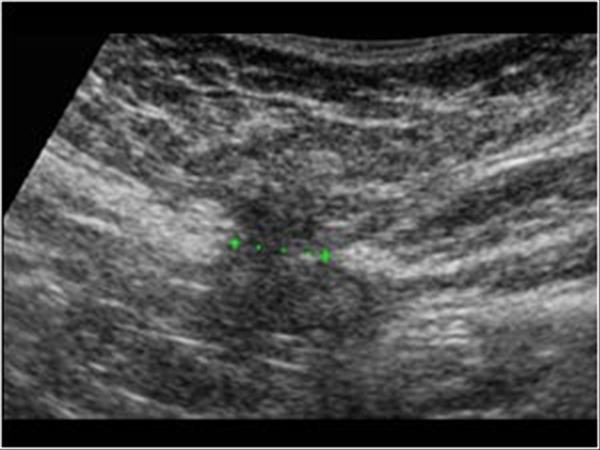

Διάγνωση

Πρώτα γίνεται κλινική εξέταση. Ο έλεγχος συμπληρώνεται με διάφορες απεικονιστικές εξετάσεις (συνήθως υπερηχογράφημα, ακτινογραφία και μαγνητική τομογραφία). Ο απεικονιστικός έλεγχος στην προκειμένη περίπτωση δεν γίνεται για να αναδείξει τη βλάβη, αλλά κυρίως για να αποκλείσει τις συχνές παθήσεις της περιοχής οι οποίες μπορούν μπορούν να προκαλούν παρόμοια συμπτώματα με της κήλης (κυρίως της βουβωνικής) και οι οποίες δεν θεραπεύονται με χειρουργική επέμβαση. Έτσι έχει μεγάλη σημασία η ερμηνεία των απεικονιστικών αυτών εξετάσεων να γίνεται από ακτινολόγο με γνώση και εμπειρία στις σχετικές παθήσεις της περιοχής, μεταξύ των οποίων περιλαμβάνονται τενοντίτιδες, θλάσεις μυών, σύνδρομα παγίδευσης νεύρων, οστεΐτιδες μικροκατάγματα εκ κοπώσεως κ.α. Τα πράγματα γίνονται ακόμα πιο περίπλοκα καθώς είναι δυνατόν ορισμένες από αυτές τις παθήσεις να συνυπάρχουν με τη βουβωνική διαταρχή κάνοντας τόσο την κλινική όσο και την απεικονιστική διάγνωση δυσχερέστερη.